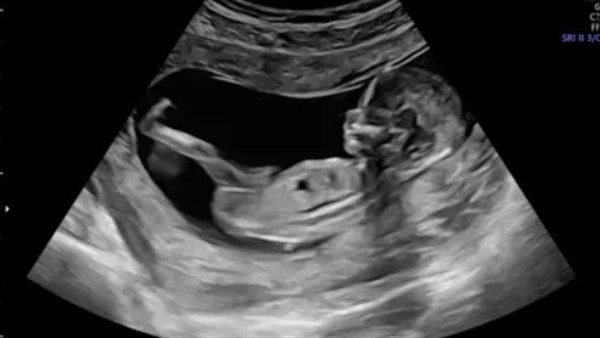

واعتمدت الدراسة على متابعة مجموعة من الحوامل في 3 مستشفيات كبرى في برشلونة، وخضع 132 طفلا حديث الولادة لفحوصات متقدمة بالرنين المغناطيسي خلال الشهر الأول لتقييم مستوى نضج أدمغتهم عبر قياس تقدم عملية الميالينة، إذ أظهرت النتائج ارتباطا واضحا بين ارتفاع التعرض للجسيمات الدقيقة أثناء الحمل وتراجع مستوى الميالينة في الدماغ.